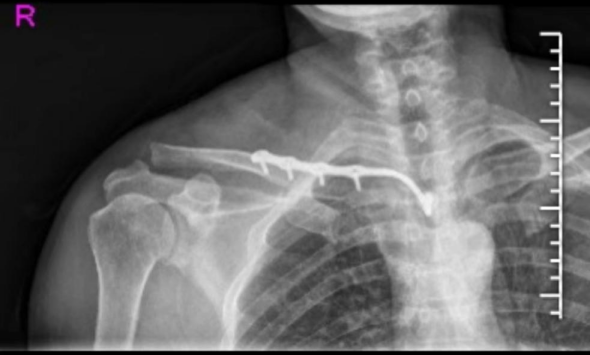

锁骨近端骨折,这样手术风险低! 锁骨近端解剖复杂,既往骨折多采用非手术治疗,预后不理想。近年来,治疗理念发生变化,手术治疗越来越多,本文整理了 胸锁钩钢板在锁骨近端骨折 的应用,供大家参考。 不说废话,先上病例 !! …

无需内固定?锁骨远端不稳定骨折全缝合技术! 锁骨远端骨折占锁骨骨折的15 %。移位的 Neer II 型和 V 型锁骨骨折通常在活动患者中进行手术治疗。然而,远端碎片固定仍然是一个挑战,关于最佳手术治疗尚未达成共识。在…